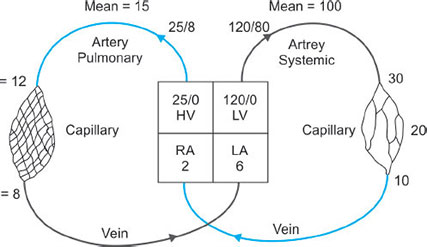

PERFUSION

Blood flow to and around the lung is similar to any other organ but at much lower pressures than the systemic system (Fig. 29).37

The blood vessels in the lungs continually branch and get consistently smaller very like the branching of the airways. The pulmonary arteries whose walls are very thin in comparison to that of the arteries in the main circulation feed the lung up to the level of the terminal bronchioles and then split into the capillary bed. The capillaries have great capability to distend thus enhancing gas exchange and reservoir action. Once the red blood cells have become oxygenated the capillary bed is drained into venules which then join to form the pulmonary veins. It is the ability of the blood vessels to distend and be recruited which allows the pressures in the pulmonary system to stay low despite very high blood flow.

The pulmonary arteries only supply blood flow and oxygen to the lungs and must have the ability to accept huge blood volumes at times. The low pulmonary pressures are important to minimize the work of the right heart.

Pulmonary Vascular Resistance

PVR = 80 × (MPAP – PCWP)/CO